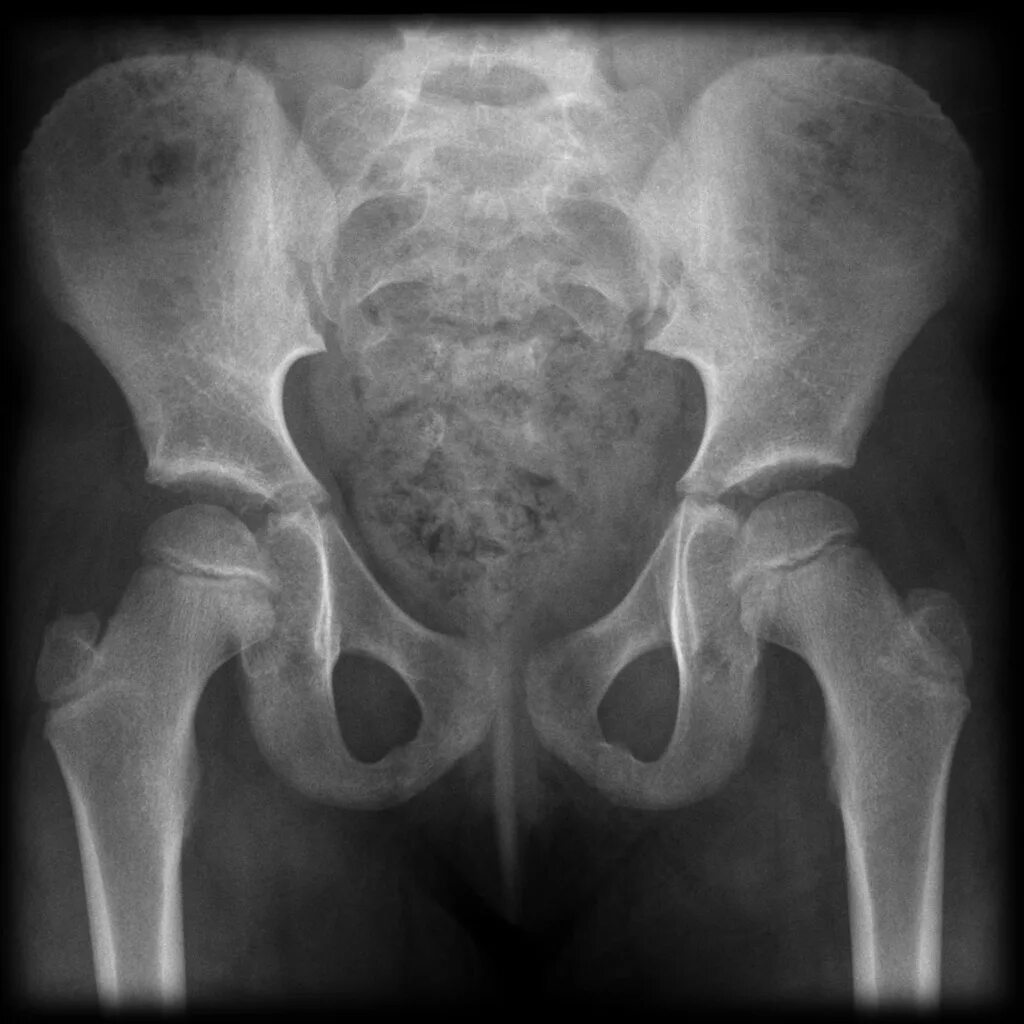

Снимок костей как называется